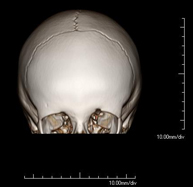

- Skull CT

Radiological test that provides high definition anatomical images of the skull (brain stem, cerebellum, cerebrum, cranial calotte, etc.) using CT (Computed Tomography) equipment. Indicated for: trauma, headache, memory disorders, sudden loss of strength in a limb or half of the body.